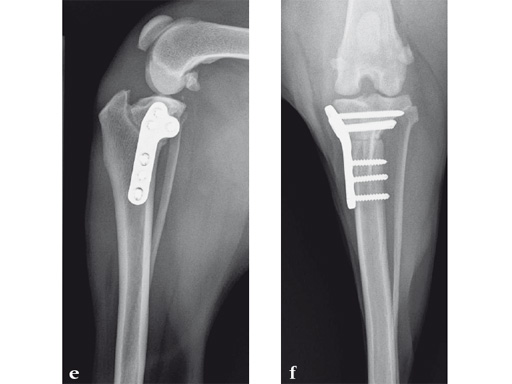

An 11-year-old female, spayed, 13.6 kg cocker spaniel had a complete tear of the left cranial cruciate ligament. A 2.4 mm TPLO plate was perfect for this dog due to the excessive slope of the tibial plateau (30) and the size of the dog. Three 2.4 mm locking screws were used proximally and three 2.4 mm cortical screws were used distally. The contour of this plate matches the contour of the bone almost perfectly. The plate is also designed to optimize the angle of the proximal screws so that they engage the most dense and thickest bone and avoids penetration of the stifle joint.

A 10-year-old female, spayed, 6.0 kg cat had a partial tear of the left cranial cruciate ligament, meniscal mineralization, and a medial meniscal tear. The cat was treated with a partial meniscectomy and TPLO . A 2.0 mm TPLO plate was perfect for this cat due to the slope of the tibial plateau (25) and the size of the cat. Three 2.0 mm locking screws were used proximally and three 2.0 mm cortex screws were used distally. The contour of this plate does not perfectly match the contour of the proximal tibia, but use of locking screws in this segment avoids any potential angulation of the segments as the screws are tightened. The cat healed uneventfully and returned to normal function.